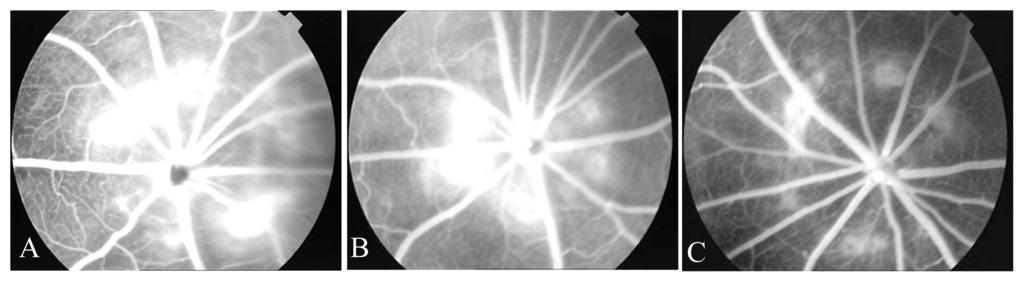

Of the 1139 laser spots observed by the 2 doctors, only 42 had different grading of fluorescein leakage. And the difference for all the spots was within 1 level. The higher grade was adopted for these 42 spots. At day 7 and day 14 following photocoagulation, the leakage rate by group was: laser injury group 40% and 67.82%; normal saline group 38% and 70.19%; endostatin group I 32.35% and 44.44%; endostatin group II 9.61% and 23.64% respectively. The intensity of fluorescein leakage was presented in tables 1 and 2. There was no significant difference between laser injury group and normal saline group. In contrast, in the 2 endostatin groups, the number of leak spots in the ocular fundus of BN rats was less and leak intensity was weaker. Furthermore, the difference became more significant as duration of endostatin treatment lasted longer, and in a dose-dependent way (Figures 1 and 2). Fluorescein angiography of ocular fundus in normal BN rats did not show fluorescein leakage (Figure 3).

Figure 2.

At day 14 after photocoagulation, FFA showed that A. laser injury group: obvious fluorescein leakage was observed in laser spots, high fluorescence was evident at early stage and fluorescent spots diffused and persisted at late stage of angiography; B. endostatin group I: 2 spots with severe leakage and 1 with moderate leakage; C. endostatin group II: only one spot of moderate leakage was seen.